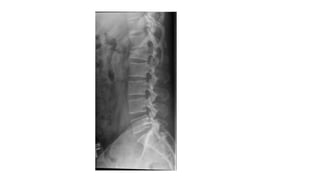

• Lordosis: spine curvature concave posteriorly

• Kyphosis: spine curvature concave anteriorly

Lordosis

• Cervical and lumbar lordoses

• Appear during the late fetal period but do not become

obvious until infancy due to extension from the flexed fetal

position

• Secondary curvatures -primarily by differences in thickness

between the anterior and the posterior parts of the IV discs.

• The cervical lordosis

• when infant begins to raise (extend) the head while prone and to hold

the head erect while sitting.

• The lumbar lordosis becomes

• when toddlers begin to assume the upright posture, standing and

walking.

• This curvature, generally more pronounced in females,

ends at the lumbosacral angle formed at the junction of L5

vertebra with the sacrum

Exaggerated lumbar lordosis (hollow back/

sway back)

• Anterior tilting of pelvis

• Increased extension of lumbar vertebrae

• Weak musculature of anterolateral abdominal

muscles

• Pregnancy, obseity